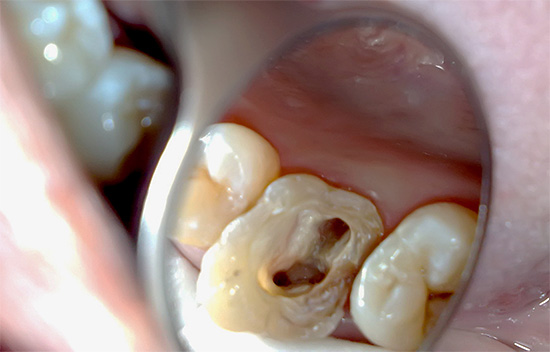

- preparazione di tessuti molli cariati con punta di una turbina, rimozione di dentina necrotica e pigmentata;

- apertura di un buon accesso alle bocche dei tre canali;

- estensione della bocca;